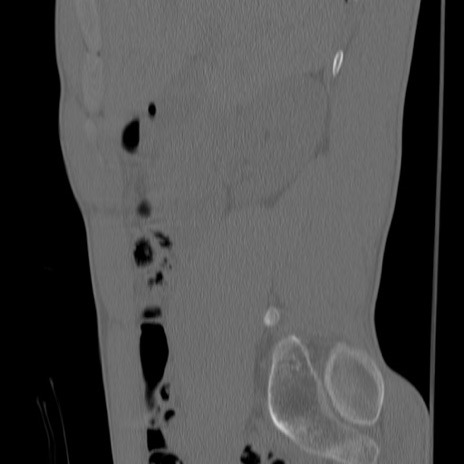

症例3 腰椎CT(矢状断像)

【症例】30歳代男性

【主訴】腰痛

【現病歴】本日旅行先で観光中に、友人と衝突し転倒し受傷。

【身体所見】麻痺なし、右下腿内側前面外側、左下腿内側に知覚鈍麻・しびれ

異常所見と診断は?

腰椎CT